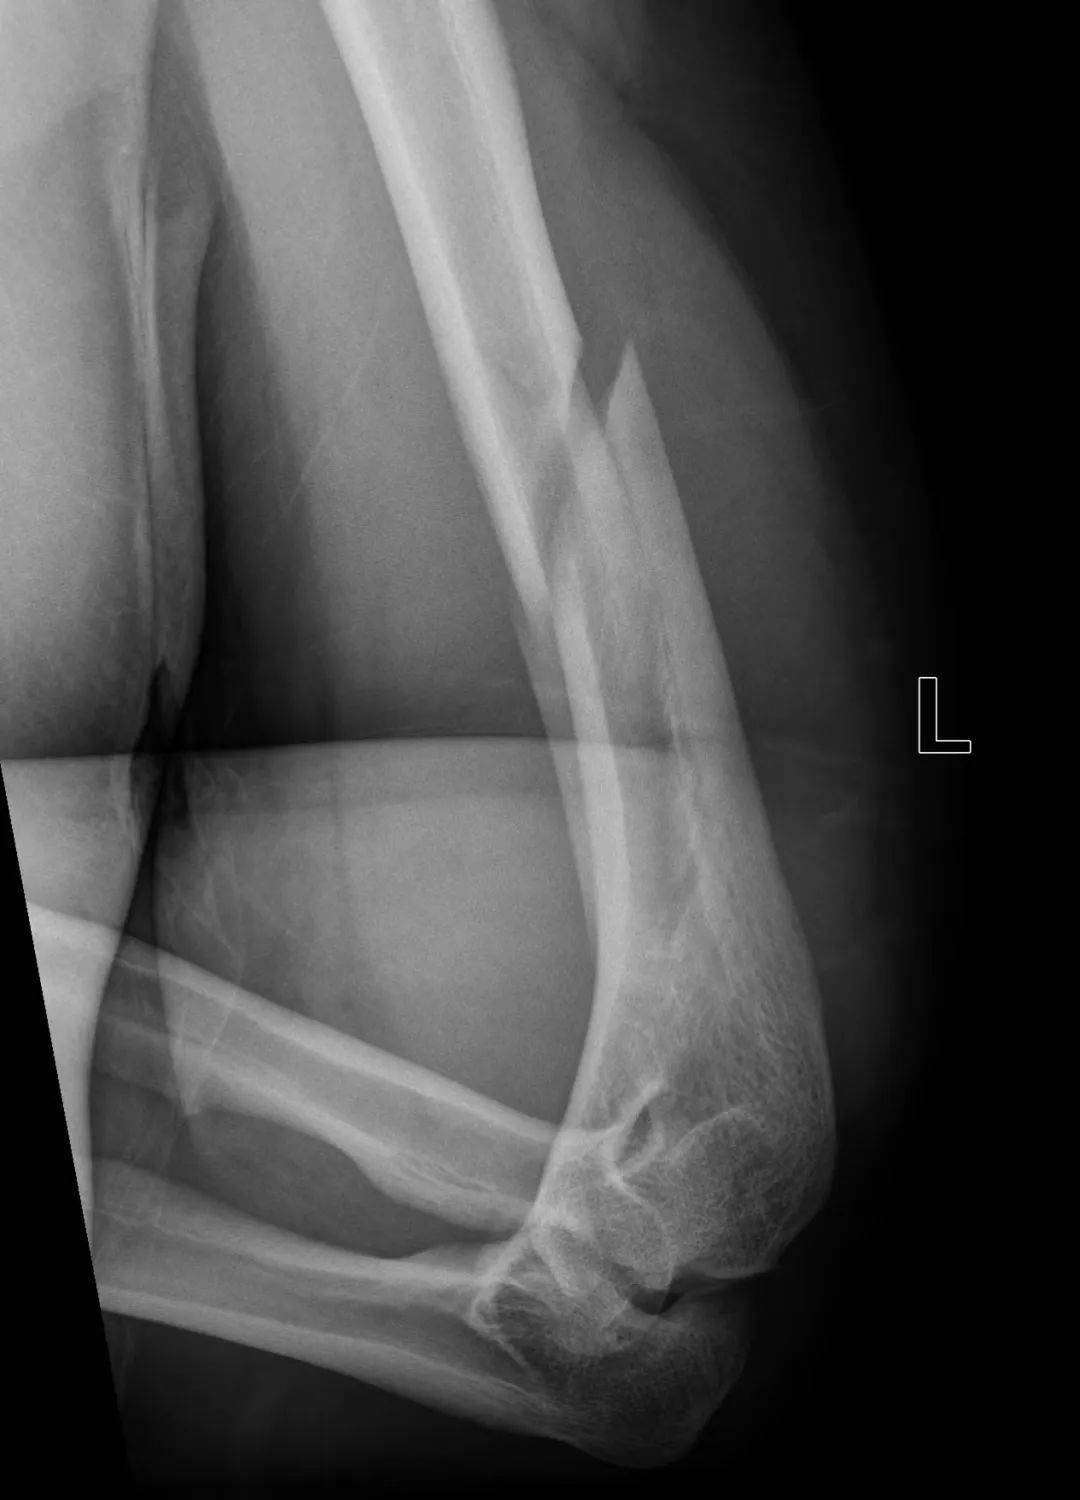

由于存在共同的受伤机制,扳手腕导致的肱骨干骨折表现极为相似。这类骨折几乎都是肱骨远端三分之一螺旋形骨折,半数伴有蝶形骨折片,在AO/OTA分型中分别为12-A1型和12-B1型,可伴有桡神经损伤。

图 扳手腕导致的肱骨干骨折